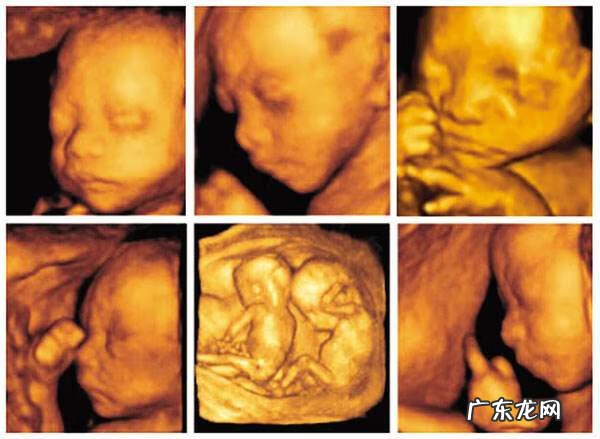

4、彩超真的是彩色的吗?

不是的,亲们 。彩超不是彩色的,无论是四维彩超还是三维的都是土黄色的 。之所以说是彩超主要是和之前的黑白B超对比的 。但是彩超的分辨率更高,看的更清晰 。三维彩超是静态的照片,四维是动态的影像 。

5、四维彩超在排畸检查上真的比三维的好吗

其实这两种在了解宝宝发育状况和排畸检查的效果上是差不多的 。关键的还是B超师的水平和耐心了,和三维和四维关系不大 。

四维彩超排畸检查不是万能的,只能外观畸形的手段 。对于智力发育,遗传疾病等筛查是做不到,你还需要另一种产检,那就是唐筛 。小编最近会为大家奉上唐氏筛查的相关内容,敬请期待